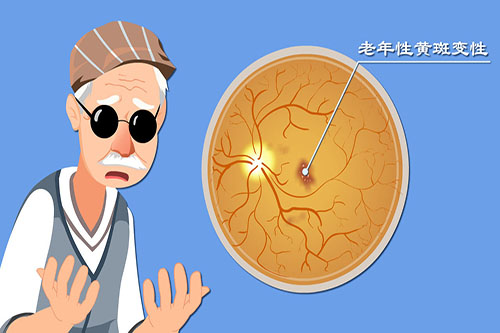

对于糖尿病视网膜病变患者,他创新性地结合抗VEGF药物注射与精密激光治疗,有效延缓病情进展。

在高度近视并发症治疗方面,孙医生采用个性化方案,针对黄斑裂孔、视网膜劈裂等病变开展精密手术干预。